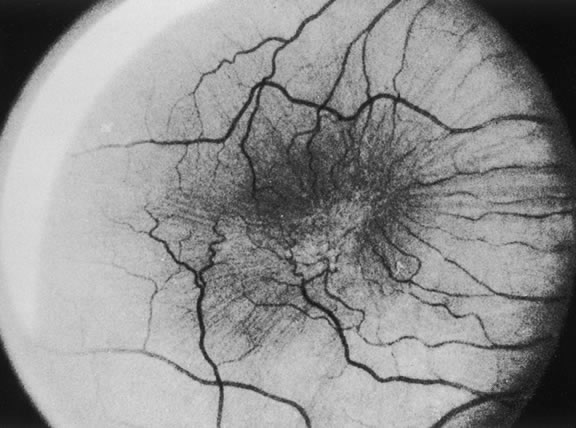

MACULAR EPIRETINAL MEMBRANES

Macular epiretinal membranes are a vitreoretinal condition characterized by cellular proliferation on the anterior surface of the ILM of the macula usually occurring after PVD. This proliferation may also occur as a result of inflammation, retinal vascular occlusion, retinal breaks, or detachment. However, there is commonly no associated ocular disease, and this proliferation is then classified as idiopathic. A number of descriptive terminologies have been applied to this condition, including preretinal macular fibrosis, surface wrinkling retinopathy, cellophane maculopathy, primary retinal folds, and macular pucker. Gass102 proposed a three-grade classification for these epiretinal membranes. Grade 0 is for translucent, shiny membranes without retinal distortion corresponding to cellophane maculopathy. Grade 1 is for membranes that have contracted or shrunk resulting in inner retinal irregular folds. Fine superficial radiating folds extending outward from the margins of the contracted membrane are often the most easily distinguished biomicroscopic evidence of an epiretinal membrane. The reduction in visual acuity from these epiretinal membranes is primarily a result of the distortion of the outer retinal layers and not a function of the thickness of opaqueness of the membrane (Fig. 21). Thicker, more opaque membranes that obscure underlying vessels and cause full-thickness retinal distortion are classified as grade 2 corresponding to macular pucker. Retinal edema, small retinal hemorrhages, cotton-wool spots and exudates may all be seen in conjunction with these more opaque membranes. Grade 2 membranes are also referred to as macular pucker (Fig. 22). In this chapter, we use the term macular epiretinal membranes, which is used to encompass the spectrum of this condition.

Fig. 22. Grade 2 epiretinal membrane.

The incidence of idiopathic macular epiretinal membranes is approximately 3.5% at autopsy, and they are unilateral in 80% of cases.103 As noted previously, the clinical appearance of macular epiretinal membranes ranges from a transparent sheet with no effect on the retina to an opaque white tissue with obscuration of the underlying retina and full-thickness retinal distortion. The membrane's effect on vision can vary greatly. Patients can present with fine translucent epiretinal membranes that may remain stable for many years, resulting in only mild visual symptoms. Patients with full-thickness retinal folds secondary to macular pucker may complain of metamorphopsia or decreased vision resulting from macular edema or localized serous detachment of the retina. Epiretinal membranes can demonstrate areas of pigmentation within the membrane, possibly secondary to migration of RPE cells. This pigmentation is most commonly found in membranes seen following repair of a rhegmatogenous retinal detachment or following a retinal tear. These pigmentary cells may be liberated into the vitreous cavity through the retinal break. Idiopathic epiretinal membranes are rarely pigmented. A PVD is present in 80% to 95% of idiopathic macular epiretinal membranes and is, therefore, believed to be important in the pathogenesis of idiopathic epiretinal membranes. It is postulated that a PVD may disrupt the ILM, resulting in the migration of retinal glial or other cells through the ILM onto the retinal surface.104 These microbreaks in the ILM may allow astrocytes, glial cells, fibroblasts, and other contractile tissue to migrate along the retinal surface, thus, forming an epiretinal membrane that may undergo contraction. Histologically, idiopathic macular epiretinal membranes consist primarily of fibrous astrocytes derived from retinal glial and RPE cells. Other cells, such as fibrocytes and myofibrocytes, are identified in 8% to 20% of cases.10 Conditions such as a retinal detachment and/or retinal tear may directly liberate RPE cells, which can proliferate on the retinal surface, into the vitreous cavity. However, because there is no full-thickness retinal disruption present by definition in idiopathic epiretinal membranes, it is unclear how RPE cells enter the preretinal space. The retinal glia can stimulate proliferation of RPE cells.105 One possible scenario for idiopathic epiretinal membranes is (1) PVD leading to disruption of the ILM, (2) migration of retinal glia through the ILM, and (3) proliferation of retinal glia resulting in stimulation of RPE cell migration through the retina and proliferation on the retina. In addition, PVDs can often result in vitreous hemorrhage from disruption of retinal blood vessels. It may be that this vitreous hemorrhage liberates cells from within the retina that may stimulate proliferation on the macular surface.